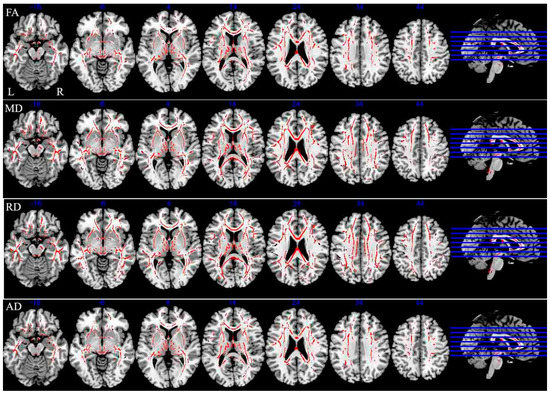

Tract-based spatial statistics (TBSS) detected significantly decreased fractional anisotropy (FA) and increased mean diffusivity (MD) and radial diffusivity (RD) in many WM tracts in MS patients compared with HCs. However, increased axial diffusivity (AD) was found to be restricted to a small number of WM tracts. Comparison of individual voxels of the WM skeleton between MS patients and HCs [10] revealed decreased FA values in 74% of the investigated WM. In addition, increased MD, RD, and AD were found in 68%, 79%, and 30% of the investigated WM, respectively, in MS patients compared with HCs (Figure 1, blue bars).

Figure 1.

Extent of white matter (WM) integrity damage in diffusion tensor images (DTI) analyses. The bars indicate the extent of WM integrity damage. The blue and red bars indicate differences of WM diffusion between the multiple sclerosis (MS) patients and healthy control (HC) subjects, and between the cognitive impairment (CI) and cognitive preservation (CP) groups, respectively. FA, MD, RD, and AD refer to fractional anisotropy, mean diffusivity, radial diffusivity, and axial diffusivity, respectively. FA: fractional anisotropy; MD: mean diffusivity; RD: radial diffusivity; AD: axial diffusivity.

Decreased FA values and increased MD and RD values were observed in a large number of WM tracts across the brain in CI compared with CP patients (Figure 1). FA was decreased in 44% of the studied WM, and almost all the areas exhibiting decreased FA overlapped with areas exhibiting increased MD and RD. Statistical analyses revealed that MD and RD values were increased by 51% and 55%, respectively, in the CI group compared with the CP group (Figure 1, red bars). However, the areas showing increased AD (30% of the investigated WM) were restricted to a small number of WM tracts, including the corpus callosum, corona radiata, external capsule, superior longitudinal fasciculus, anterior limb of internal capsule, middle cerebellar peduncle, fornix (cres)/stria terminalis. In addition, these areas overlapped with regions exhibiting reduced FA, increased MD and RD (pFWE correction < 0.05) (Figure 3 and Table 3).

Figure 3.

Tract-based spatial statistics (TBSS) analysis results of diffusion metrics images throughout the skeleton in CI patients compared with MS patients with CP. R: right; L: left. Red represents regions with decrease fractional anisotropy (FA), increased mean diffusivity (MD), increased radial diffusivity (RD) and increase axial diffusivity (AD) in CI patients with MS (p < 0.05, FWE corrected for multiple comparisons).